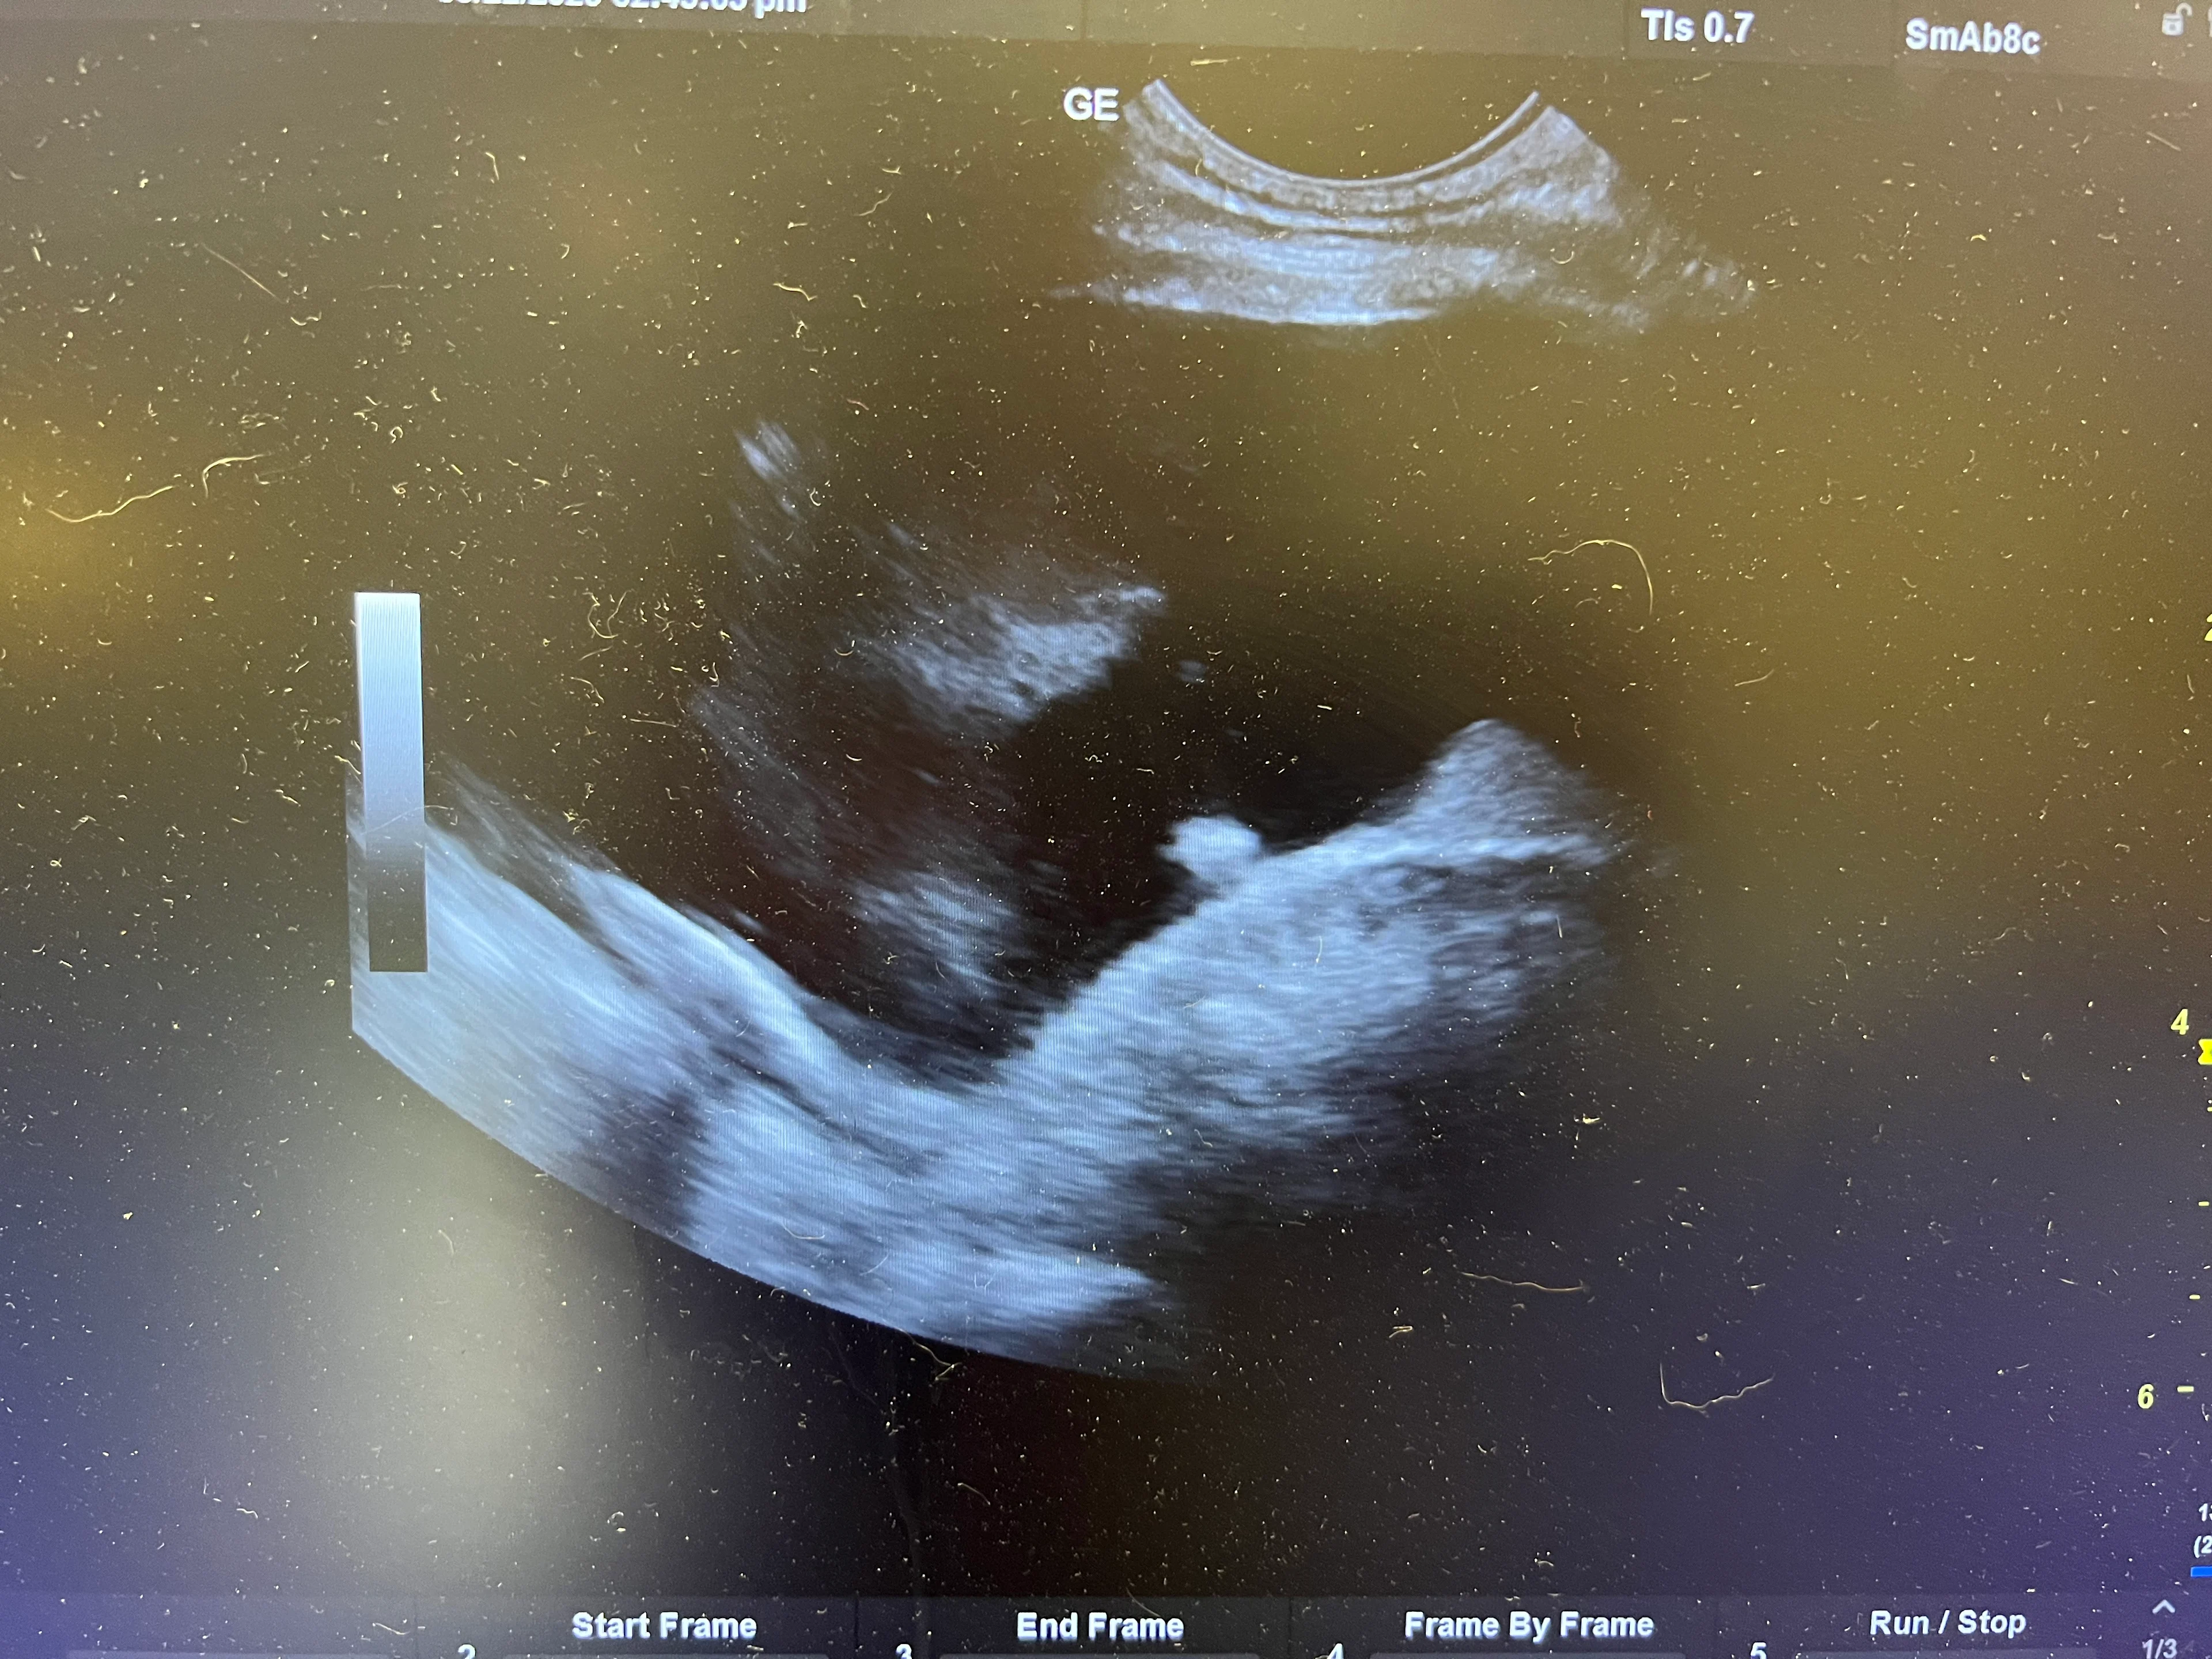

On ultrasound, pleural effusion appears as an anechoic pocket separating the lung lobes from the thoracic wall.